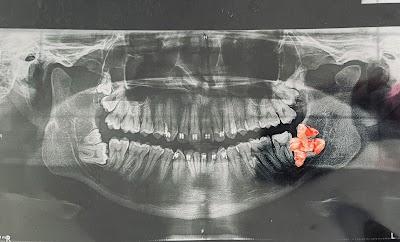

Cabo Dental Care es un profesional dental dedicado especializado en Odontología General en San José del Cabo. Con un compromiso hacia la comodidad del paciente y la excelencia clínica, la clínica ofrece atención dental integral utilizando técnicas y equipos modernos. Cada paciente recibe atención personalizada en un ambiente acogedor y profesional. El equipo se enfoca en crear una experiencia libre de estrés mientras entrega resultados sobresalientes. Ya sea que necesite atención de rutina o tratamientos especializados, puede confiar en Cabo Dental Care para servicios dentales de calidad. Agende su cita hoy y dé el primer paso hacia una sonrisa más saludable y brillante.

- ✓ Diagnóstico Digital